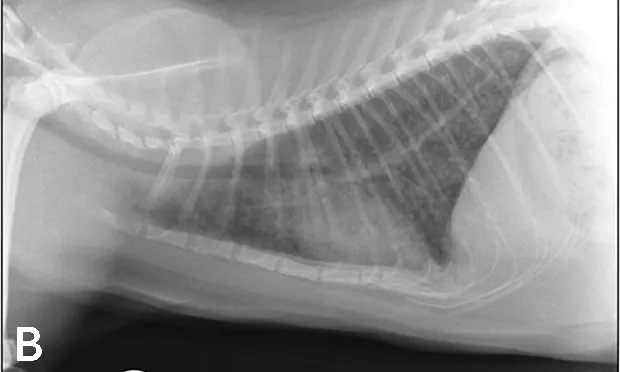

Luna was placed in an oxygen-enriched cage, and thoracic radiographs (Figure 1) were taken.

Figure 1. Thoracic radiographs taken at presentation.

Luna’s clinical signs and radiograph findings were most consistent with lower airway disease (ie, feline asthma). While asthma implies reversible bronchoconstriction, some cats with lower airway disease have more inflammatory changes and less reversible airway changes.

Radiographic findings consistent with airway disease include donuts and tram lines, which are supportive of bronchial thickening and hyper­inflation from expiratory flow limitation. Some cats with lower airway disease also have a collapsed middle lung lobe (Figure 2).